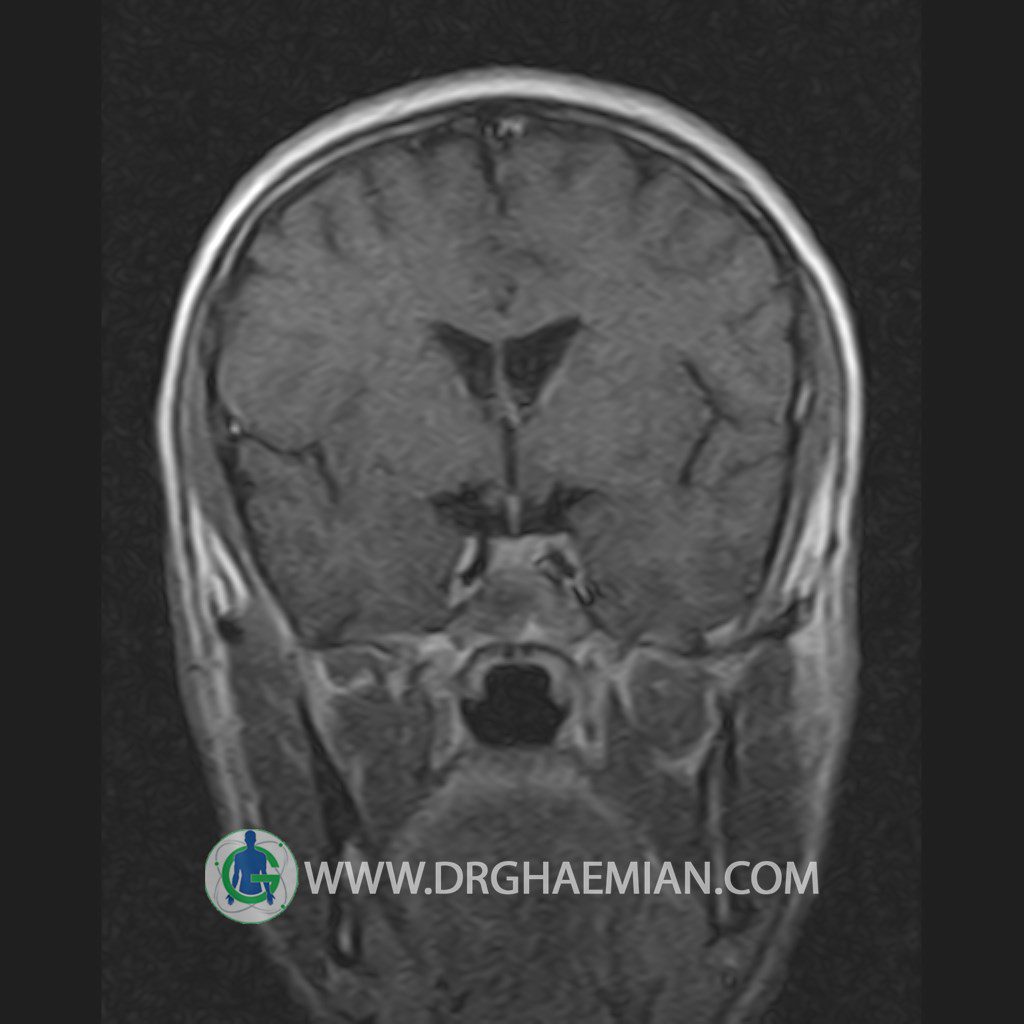

پزشکان اغلب از تصویربرداری ام آر آی برای تشخیص و درمان عارضه های پزشکی که فقط با استفاده از اشعه ایکس یا میدان مغناطیسی و امواج رادیویی قابل مشاهده است، استفاده می کنند. دستگاه ام آر آی تصاویر دقیق از ساختار های داخلی بدن ایجاد می کند. در این کیس یک میکروآدنوم در هیپوفیز بیمار مشاهده می شود.

HYPOPHYSIS MRI

(with and without contrast)

Technique: Axial , coronal T1 , Axial , coronal , sagittal T2 , Axial, coronal T1 post Gd & 64 dynamic thin coronal slices.

REPORT :

The infundibulum is centered and of normal size .

The optic chiasm and suprasellar spaces appear normal .

The cavernous sinus and imaged portions of the internal carotid artery and carotid siphon are unremarkable .

– Small hypoenhancing mass lesion ( 3 x 4 mm ) in posterior of pituitary stalk suggestive for micro adenoma